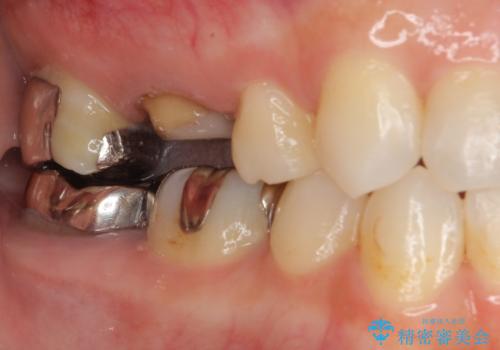

適合もよく、機能的に問題もなく、見た目も満足されていました。

今後はメンテナンスで通ってもらいながら、ほかの部位の金属の詰め物が気になったらセラミッククラウンに変えていく予定です。